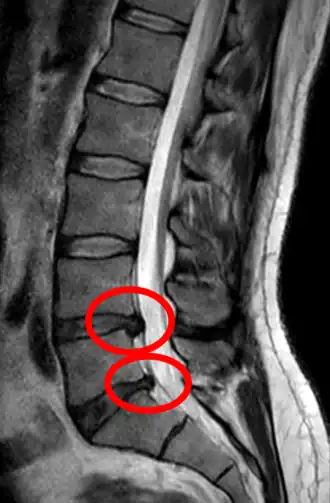

L'imagerie par résonance magnétique peut montrer la hernie, le canal vertébral, les nerfs, les tissus environnants. Les tissus mous sont les mieux analysés par cet examen qui est le plus performant pour le diagnostic de hernie discale. Les images pondérées en T2 montrent clairement la hernie.

IRM lombosacrée sagittale montrant une hernie discale de niveau L4-L5.

IRM lombaire sagittale montrant une hernie discale de niveau L4-L5.

IRM lombaire sagittale montrant une hernie discale de niveau L4-L5.- IRM lombaire sagittale montrant des protrusions discales.